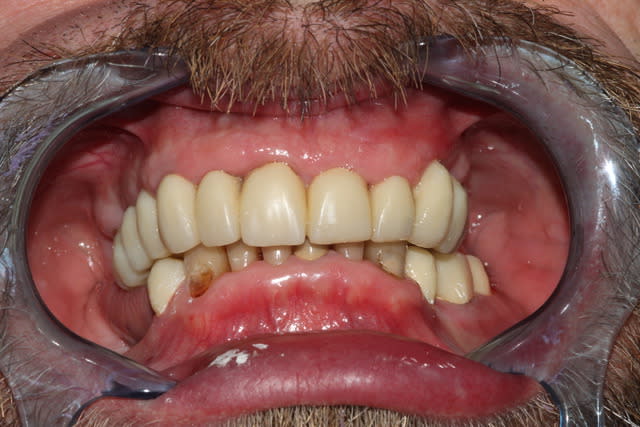

Bon allez, du coup je me lance.

Encore une fois, plusieurs décisions sont critiquables, et j'avais au moins 10 possibilités en tête pour le bonhomme. (et sur des cas comme ça, en comparaison de ce que font certains ici, je me sens tout petit, mais bon...)

En l’occurrence, 2 devis proposés: un amovible, minimum: extractions multiples, refaire ce qui doit l'être d'urgence et stellite haut et bas; et un tout fixe.

Le patient réfléchit, revient 3 mois plus tard: ok pour le fixe, boulot commencé en septembre.

En prévision: bridge complet 16-26 en haut (extension en 26), bridge secteur 3 en bas, implants 45 46.

En tout, boulot réalisé sur une quinzaine de séances, contrôles et réglages inclus.

Au départ, je pensais extraire 17,12 et 23.

La paro a été gérée "en continu", tout du long: détartrages supra gingivaux et irrigations éventuelles à chaque séance. L'hygiène est parfaitement suivie du début à la fin.

Première séance de préparation: ex 17, dépose des couronnes sans antagonistes pour se faciliter un peu le boulot de la deuxième séance, empreintes primaires.

Deuxième séance, 2h30 si mes souvenirs sont bons: préparations de tout le maxillaire, et pose du bridge pro avec une DV remontée de quelques mm. DSR manuel des poches profondes, curetage rotatif à la touati de toutes les préparations, l'accès visuel est largement simplifié.

La 12 est finalement conservée, la 24 finalement extraite.

Petit imprévu: impossible de sortir la 23, trop délabrée: je ne me sens pas de lever un lambeau lors de cette séance déjà longue, on la laisse en place pour l'instant.

Contrôle 2 jours plus tard, la nouvelle DV est bien supportée.

Les courbes occluasles ne sont pas alors idéalisées (la 36 gêne, et secteur 1 on la règlera à la plaque de fox par la suite)

Photos de l'occlusion avant les réglages occlusaux, tout juste sorti du labo. J'ai diminué les contacts sur la 23 en entrée de cycle, et sur la 21 en incision. (bleu en statique, rouge en cycles masticatoires)

Pose des implants prévue pour cet été, donc couronnes vers Noël probablement.

Je peaufinerai probablement encore un peu l'occlusion dans 6 mois, lorsqu'on posera 45 46.